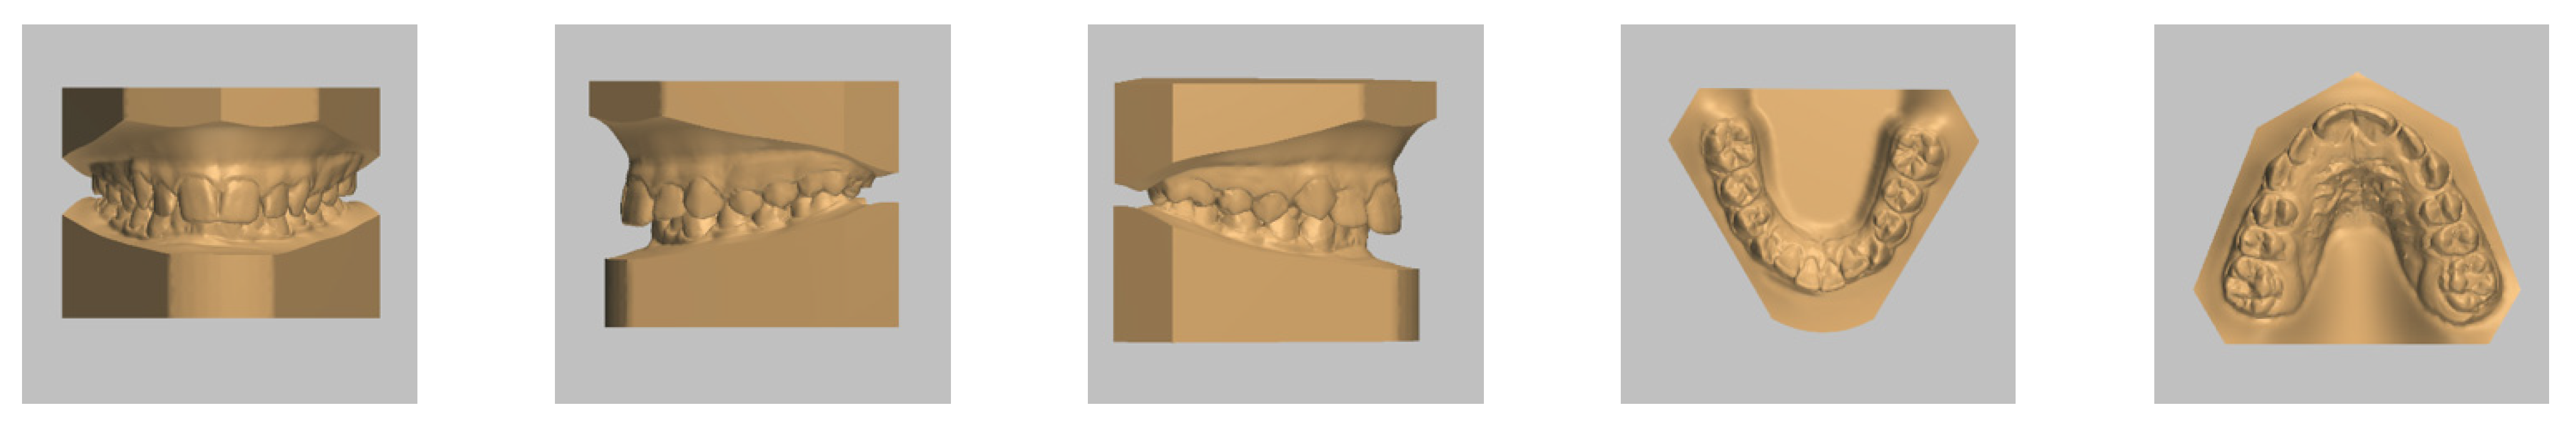

4. Case Report

4.1. Etiology and Diagnosis

4.2. Treatment Objectives

4.3. Treatment Strategy

4.4. Treatment Progress